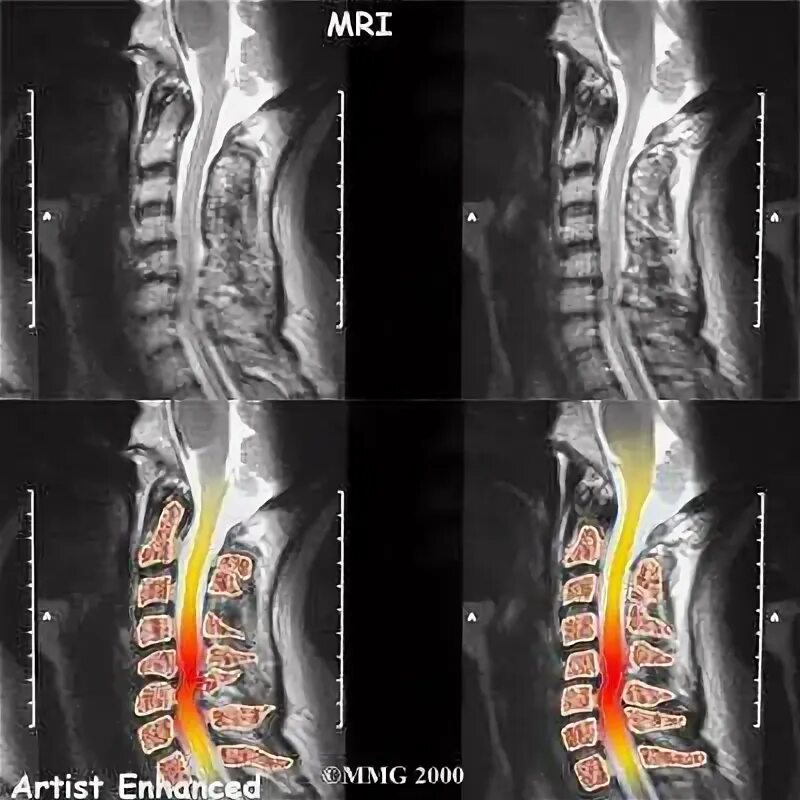

Перед мрт позвоночника можно кушать